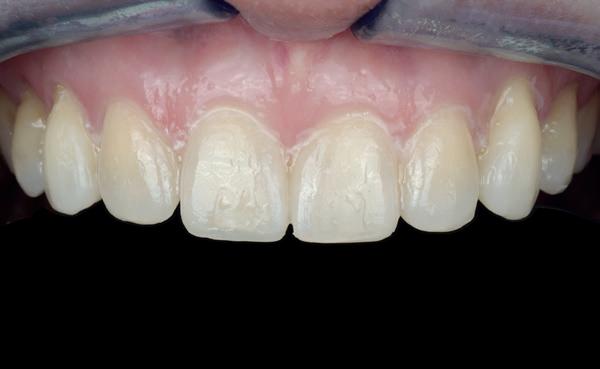

Een 47-jarige vrouw wordt aan het einde van het orthodontische traject door haar eigen tandarts naar mij verwezen voor een intake en eventuele behandeling. Bij mevrouw zijn elementen 12 en 22 afwezig. De 13 en 23 zijn gemesialiseerd. Haar eigen tandarts vraagt of ik het front met composiet kan restaureren om weer een harmonieuze glimlach te krijgen (Afbeelding 1).

Tijdens de intake wordt een complete lichtfoto status gemaakt om de positie van de elementen goed in kaart te brengen en een behandelplan op te kunnen stellen. Op de close-up foto van het bovenfront (afbeelding 2) zien we dat er sprake is van slijtage aan element 11. Elementen 12 en 22 zijn afwezig en elementen 13 en 23 zijn gemesialiseerd. Tussen element 11 en 13 is er sprake van een diasteem. Dit diasteem is niet aanwezig aan de andere zijde (afbeelding 3).

Dit zorgt voor een lastige situatie, omdat bij het sluiten van dit diasteem (dit is de wens van de patiënt) elementen 13 en 11 breder zullen worden dan elementen 21 en 23. Dit is één van de redenen waarom ik patiënten altijd graag aan het einde van het orthodontist traject wil zien. Op dat moment is het nog mogelijk om kleine wijzigingen door te voeren, voordat de beugel definitief wordt verwijderd. Na de intake stuur ik een terugrapportage naar de orthodontist waarbij ik vraag om de elementen zo te positioneren dat de ruimte beter verdeeld is.

Ik zie mevrouw een aantal weken later terug voor evaluatie (afbeelding 4). Er is een klein centraal diasteem ontstaan en daardoor is het diasteem tussen de 11 en 13 ook kleiner geworden. Tussen de 21 en 23 is geen diasteem aanwezig (afbeelding 5), waardoor er hoogstwaarschijnlijk wel iets breedte verschil zal zijn tussen de linker- en rechterzijde.

Met composiet wordt een snelle mock-up gemaakt om te beoordelen of ik in deze situatie goed kan uitkomen met de ruimte, of dat we wellicht de elementen nog meer moeten verplaatsen (afbeelding 6). Mevrouw is zeer tevreden met de snelle mock-up en daarom wordt besloten dat de orthodontische behandeling afgerond kan worden. Eventuele verschillen in breedte kunnen we proberen optisch zoveel mogelijk te maskeren.

Nadat de vaste apparatuur verwijderd is (afbeelding 7 en 8), zie ik mevrouw voor het maken van een afdruk/scan ten behoeve van een wax-up. Aangezien ik in deze casus wil werken met de injectietechniek, is een wax-up noodzakelijk.

1: Glimlach foto om de positie van de elementen ten opzichte van de lippen te beoordelen.

2: Close-up foto van de voortanden in de bovenkaak.

3: Occlusale foto om de positie van de elementen en de diastemen te beoordelen.

4: Situatie na orthodontische aanpassingen.

5: Occlusale foto om de nieuwe positie van de elementen te beoordelen.

6: Snelle mock-up met composiet om te bepalen of de huidige stand van de elementen de ruimte biedt om de elementen in de juiste vorm op te bouwen.

7: Glimlach foto na verwijderen van de vaste apparatuur.

8: Close-up foto van voortanden na verwijderen vaste apparatuur.